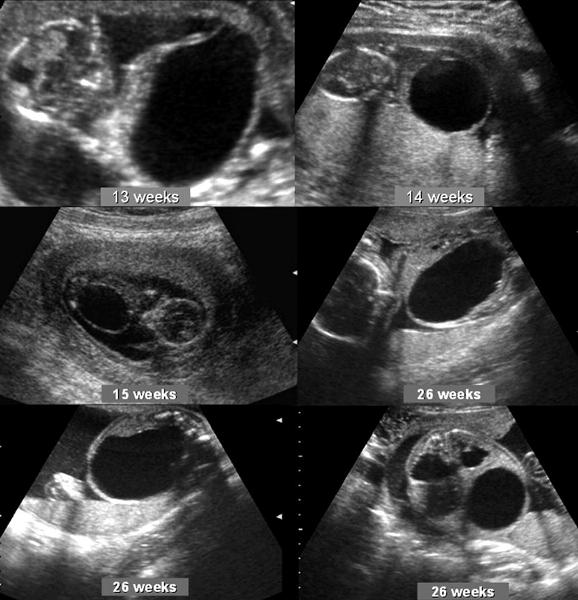

When should the kidneys and the bladder be seen?

15 weeks

Hydronephrosis

What is the most common fetal anomaly?

hydronephrosis

What is hydronephrosis usually caused by?

UPJ or UVJ obstruction

What is hydronephrosis?

Dilation of the renal pelvis due to blockage

Pyelectasis

What is pyelectasis?

abnormal collection of urine within the renal pelvis 5-9 mm

Caliectasis

Caliectasis

What is calyectasis?

rounded calyces with renal pelvis dilatation